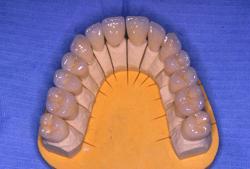

Dents provisoires réalisées au laboratoire

Les 8 dents provisoires sont mises en place.

Noter la béance antérieure qui résulte de la mise en place des dents provisoires sur les secteurs postérieurs

Couronnes céramo-céramiques. Réalisation prothétique Claude VALTIN (Paris).